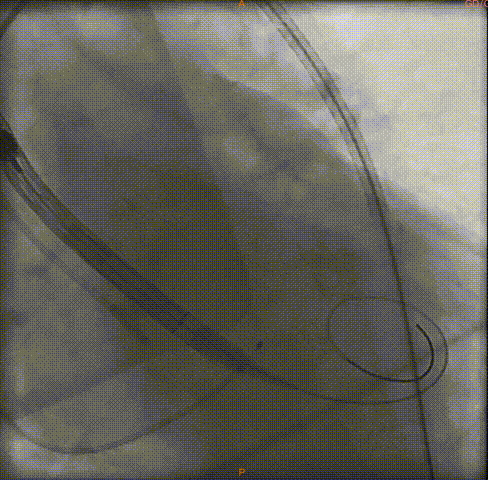

瓣膜定位

瓣膜释放

瓣膜完全释放前造影

完全释放中造影

释放后的造影

在多学科合作下,广州中医药大学第一附属医院心血管内科吴伟、李荣教授团队顺利完成全院首台高龄患者TAVR手术,经过3个小时的紧张有序操作,术中借助VitaFlow Liberty™瓣膜段柔顺性、可360度弯曲的功能顺利过弓,更是凭借心通医疗可回收系统自带内联鞘的功能,省去大鞘为血管入路差的患者带来更多选择,术后超声血管造影下肢入路无夹层且血管无破损,病人术后恢复良好,第三天即可下床活动。